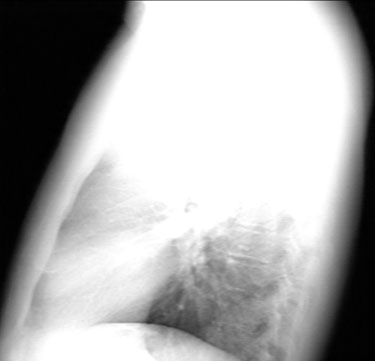

Note the large anterior mediastinal mass.